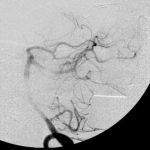

脳血管撮影

手術前

手術後